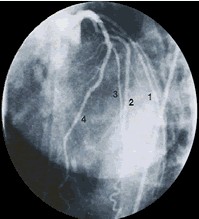

前/后位:左冠状动脉 |

1.第一边缘支 2.回旋支 3.冠状动脉左前降支 4.边缘支因脊柱和胸骨的重叠,前后位很少用。 |